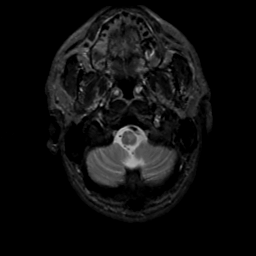

MR Study #10, April 28, 1991 -- Slice #4